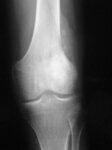

Osteossarcoma

Radiografia convencional, incidência anteroposterior (AP); lesão permeativa mal circunscrita envolvendo a metáfise femoral distal com aparência radiodensa e radioluzente mista; uma grande massa de tecidos moles com reação periosteal também está presente

Do acervo do Dr. Michael J. Klein e da Dra. Luminita Rezeanu